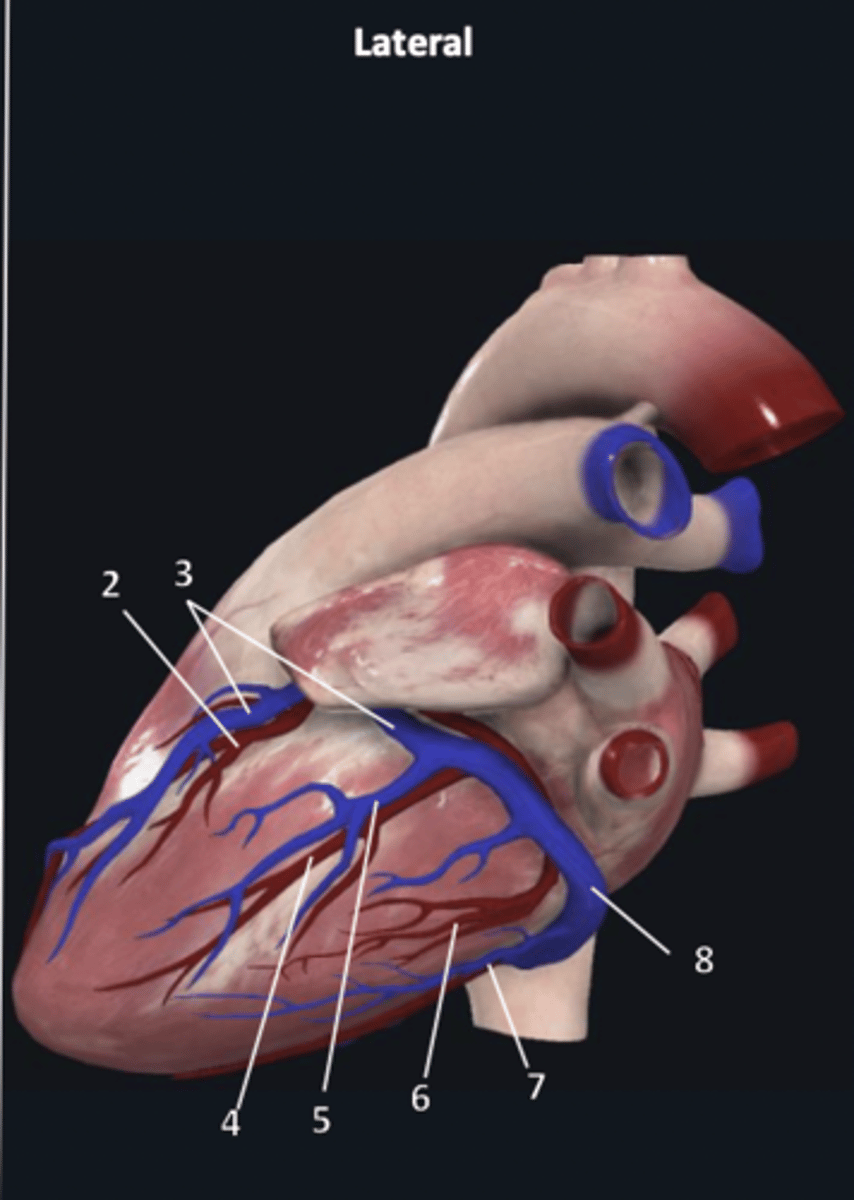

right coronary artery

1

anterior interventricular artery

2 (red)

great cardiac vein

3 (blue)

anterior interventricular artery

2 (red)

great cardiac vein

3 (blue)

left marginal artery

4

left marginal vein

5

posterior left ventricular artery

6

posterior vein of left ventricle

7

coronary sinus

8